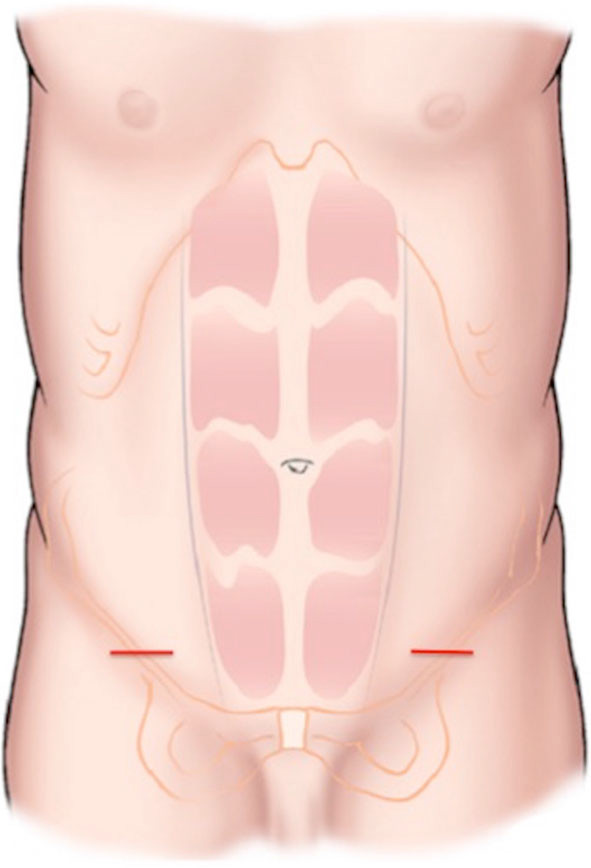

La voie d’abord est réalisée par une incision inguinale de 4cm directement au-dessus de l’anneau superficiel. La dissection s’étend du fascia de Scarpa à l’aponévrose oblique externe (figure 2). S’il existe des fissures au niveau de cette aponévrose, elles sont suturées car elles peuvent être responsable de neuropathies d’enclavements.

Figure 2 : localisation de l’incision.